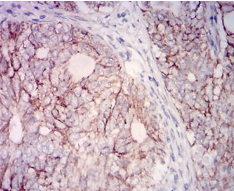

IHC    1/200 - 1/1000